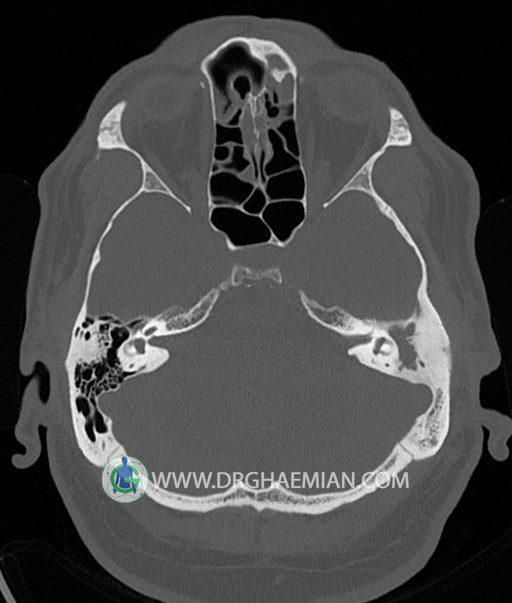

سی تی اسکن گوش داخلی به رادیولوژیست اجازه می دهد تا سطوح مختلف، یا اسلایس هایی از استخوان های که از جمجه به گوش می روند را از طریق امواج ایکس چرخشی مشاهده کند. در این کیس اودیت مدیا، ماستوئیدیت مزمن، اوتیت خارجی، انحراف سپتوم بینی، کونکا بولوزا و افزایش ضخامت سینوس ها مشاهده می شود.

گزارش پزشک :

در HRCT از استخوان تمپورال با مقاطع آگزيال ، ساژيتال و کرونال ظريف ( 0.6 mm ) :

– اپاسيتي گوش مياني چپ ناشي از وجود دانسيته نسج نرمي دراطراف استخوانچه ها همراه با اروژن اسکوتوم و

استخوانچه ها بدون جابجايي در رديف استخوانچه ها مشهود است که مطرح کننده اوتيت مديا همراه با نشانه

هاي مشکوک به کولستئاتوم مي باشد .

– اپاسيتي و اسکلروزيس ماستوئيد چپ نشانه ماستوئيديت مزمن

– اپاسيتي کانال گوش خارجي ناشي از دانسيتي نسج نرمي مطرح کننده external otitis